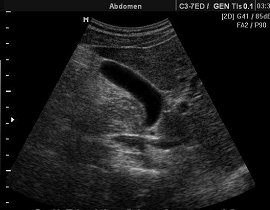

Диагностические возможности УЗД хорошо

реализуются в диагностике первичных и вторичных опухолей и сопутствующей

патологии печени, поджелудочной железы, селезенки, почек, простаты, матки,

внеорганных и брыжеечных новообразований брюшной полости, забрюшинного

пространства и малого таза. УЗД при опухолях желчного пузыря, яичников и

надпочечников имеет высокую чувствительность при малой специфичности (выявляет

соответствующие изменения, но не позволяет уверенно провести дифференциальную

диагностику). Основное предназначение УЗД - получение прямого непосредственного

изображения опухоли (гиперэхогенные и гипоэхогенные образования) и

сопутствующих изменений.

УЗИ печени УЗИ почек

УЗИ пожделудочной железы

УЗИ матки

УЗИ мочевого пузыря УЗИ желчного пузыря